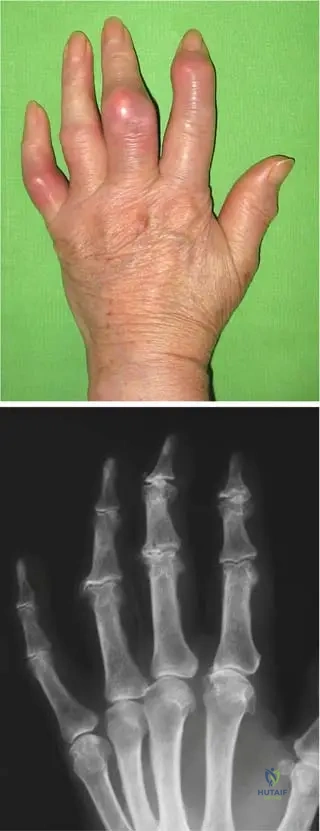

A 70-year-old male presents with chronic, progressively worsening hand deformities. On examination, his fingers are deformed, and the phalangeal joints are swollen with tight, hot, and dark-red skin. He also reports occasional low-grade fever.

View Answer & Explanation

Correct Answer: C

Rationale: The clinical context for Fig. 7.2 a, b directly describes this scenario as "Exacerbation of a chronic gout process in the hand: the fingers are deformed, the joints of the phalanges are swollen, with tight, hot, and dark-red skin, frequently accompanied by some general symptoms (fever, higher sedimentation rate, increased number of white blood cells)." While acute symptoms are present, the underlying chronicity and deformities point to an exacerbation of a chronic condition.

Question 38

A 68-year-old male with a long history of gout presents with chronic hand pain and deformities. A radiograph of his hand is obtained.

Rationale: The clinical context for Fig. 7.2 b states that the radiograph of a patient with chronic gout presents "narrowed joint spaces, and typical punched-out periarticular lytic lesions." These are classic radiographic findings for chronic gouty arthropathy. Option B describes some features that can be seen, but "punched-out lytic lesions" are highly characteristic.

Question 39

A 75-year-old male with poorly controlled gout for several decades presents with multiple firm, non-tender nodules in his palmar region.

Rationale: The clinical context for Fig. 7.3 a, b explicitly states, "Late stage of gout: numerous subcutaneous tophi are present in the palmar region." Tophi are characteristic subcutaneous deposits of urate crystals in chronic, uncontrolled gout. Heberden's and Bouchard's nodes are associated with osteoarthritis, and rheumatoid nodules with rheumatoid arthritis.

Question 40

A 72-year-old male with a history of chronic gout presents with hand pain. Radiographs reveal soft tissue masses around the small joints of the hand.

Rationale: The clinical context for Fig. 7.3 b states, "These tophaceus gouty deposits are also visible in the radiograph around the small joints of the hand." Tophi are the hallmark of late-stage chronic gout and can appear as soft tissue masses on radiographs. Chondrocalcinosis is calcification of cartilage, typically associated with pseudogout.

A 72-year-old male with a 20-year history of gout presents with progressively worsening hand pain and stiffness. Radiographs of his hands are obtained. Which of the following radiographic findings is characteristic of chronic gouty arthropathy?

Rationale: The clinical context for Fig. 7.2 b explicitly states, "The radiograph of the same patient presents the characteristics of chronic gouty arthropathy, narrowed joint spaces, and typical punched-out periarticular lytic lesions." This directly matches option C. The other options describe features of other arthropathies (e.g., osteoarthritis, psoriatic arthritis, rheumatoid arthritis).

Question 43

A 75-year-old male with long-standing, poorly controlled gout presents with multiple firm, painless nodules under the skin of his palms and around his finger joints. These nodules are consistent with the late stage of gout. Which image best depicts this clinical finding?

Correct Answer: B

Rationale: Fig. 7.3 a is described as "Late stage of gout: numerous subcutaneous tophi are present in the palmar region." This directly corresponds to the patient's presentation of firm, painless nodules (tophi) in the palmar region. Fig. 7.2 a shows an acute exacerbation, Fig. 7.4 shows acute knee gout, Fig. 7.9 shows olecranon bursitis, and Fig. 7.10 a shows intraoperative tophi, none of which are the primary clinical depiction of subcutaneous tophi in the hand.

A 65-year-old male with a history of chronic gout presents with significant deformities in his hands. Radiographs are ordered to assess the extent of his disease. In the late stage of gout, what specific radiographic finding related to deposits would be expected around the small joints of the hand?

Rationale: The clinical context for Fig. 7.3 b states, "These tophaceus gouty deposits are also visible in the radiograph around the small joints of the hand." This directly answers the question. While other findings like joint effusions or subchondral cysts might be present, tophaceous deposits are a specific characteristic of late-stage gout visible on radiographs.